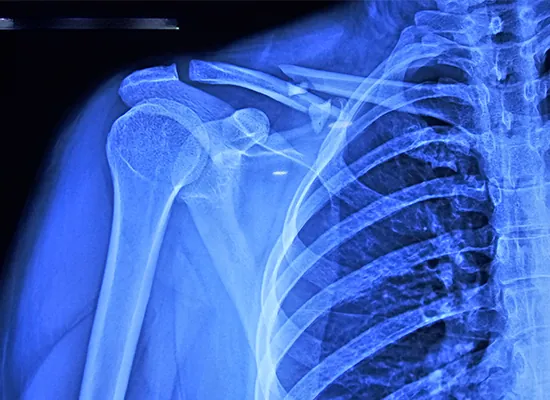

بۇ بىمار 34 ياشلىق ئايال بولۇپ ، ئالماننىڭ 1-تۈرىگە ئايرىلغان ئوڭ داس سۆڭىكى سۇنۇپ كەتكەن ، يەنى بۇ ئوتتۇرا ئوق سۇنغان. بۇ خىل زەخىملىنىش توغرا بىر تەرەپ قىلىنمىسا دائىم ئەگەشمە كېسەللىكلەرنى كەلتۈرۈپ چىقىرىدۇ. دوختۇر پېدرو بىمارنىڭ ئەھۋالىنى تەكشۈرگەندىن كېيىن ۋە ئۇنىڭ تەسۋىر ھاسىل قىلىش نەتىجىسىنى تەكشۈرگەندىن كېيىن ، S كلاۋىك قۇلۇپلاش تاختىسى بىلەن ئوچۇق كېمەيتىش ۋە ئىچكى ئوڭشاش (ORIF) تەرتىپىنى تەۋسىيە قىلدى.

بۇ ئوپېراتسىيە مەخسۇس S كلاۋىكلىق قۇلۇپ تاختىسىنى ئىشلىتىپ ، كۆپ پارچە سۇنۇقلارنىڭ مۇقىملىقىنى تەمىنلەش ئۈچۈن لايىھەلەنگەن ئىلغار كۆچۈرۈلگەن. 8 تۆشۈكلۈك تەخسە ئېنىق ماسلىشىشچانلىقى ۋە ساقىيىش جەريانىدا سۇنۇقنى قوللاش ئىقتىدارى سەۋەبىدىن تاللانغان. ئوپېراتسىيە ئوڭۇشلۇق بولدى ، جەرياندا ھېچقانداق ئەگەشمە كېسەللىكلەر كۆرۈلمىدى.

بىمار ئوپېراتسىيىدىن 24 سائەت كېيىنلا دوختۇرخانىدىن چىقىپ ، داۋالاش ئۇسۇلىنىڭ ئۈنۈمىنى كۆرسەتتى. ئوپېراتسىيىدىن كېيىنكى ئالتە ھەپتە ئىچىدە تارتىلغان سۈرەتتە سۇنۇقنىڭ پۈتۈنلەي ساقىيىپ كەتكەنلىكى ، بىمارنىڭ كۈندىلىك پائالىيىتىنى بىئارام بولماي ئەسلىگە كەلتۈرەلەيدىغانلىقى كۆرسىتىلدى. بۇ تېز ئەسلىگە كېلىش سۆڭەك ئوپېراتسىيىسىدە S كلاۋىك قۇلۇپلاش تاختىسىغا ئوخشاش زامانىۋى كۆچۈرۈشنىڭ ئەۋزەللىكىنى گەۋدىلەندۈردى.

كۆچۈرۈلگەن تىپ: S كلاسسىك قۇلۇپلاش تاختىسى

چوڭلۇقى: 8 تۆشۈك ، ئوڭ تەرەپ

ماتېرىيال: تىتان قېتىشمىسى كۈچلۈك ۋە چىداملىق

S شەكىللىك كونتېينېر كلاۋىكنىڭ ئاناتومىيىسىگە ماس كېلىدۇ ، بېسىمنى تەكشى تەقسىملەپ ، كۆچۈشنىڭ بوشىشىپ كېتىشى ياكى كۆچۈشىنىڭ ئالدىنى ئالىدۇ.